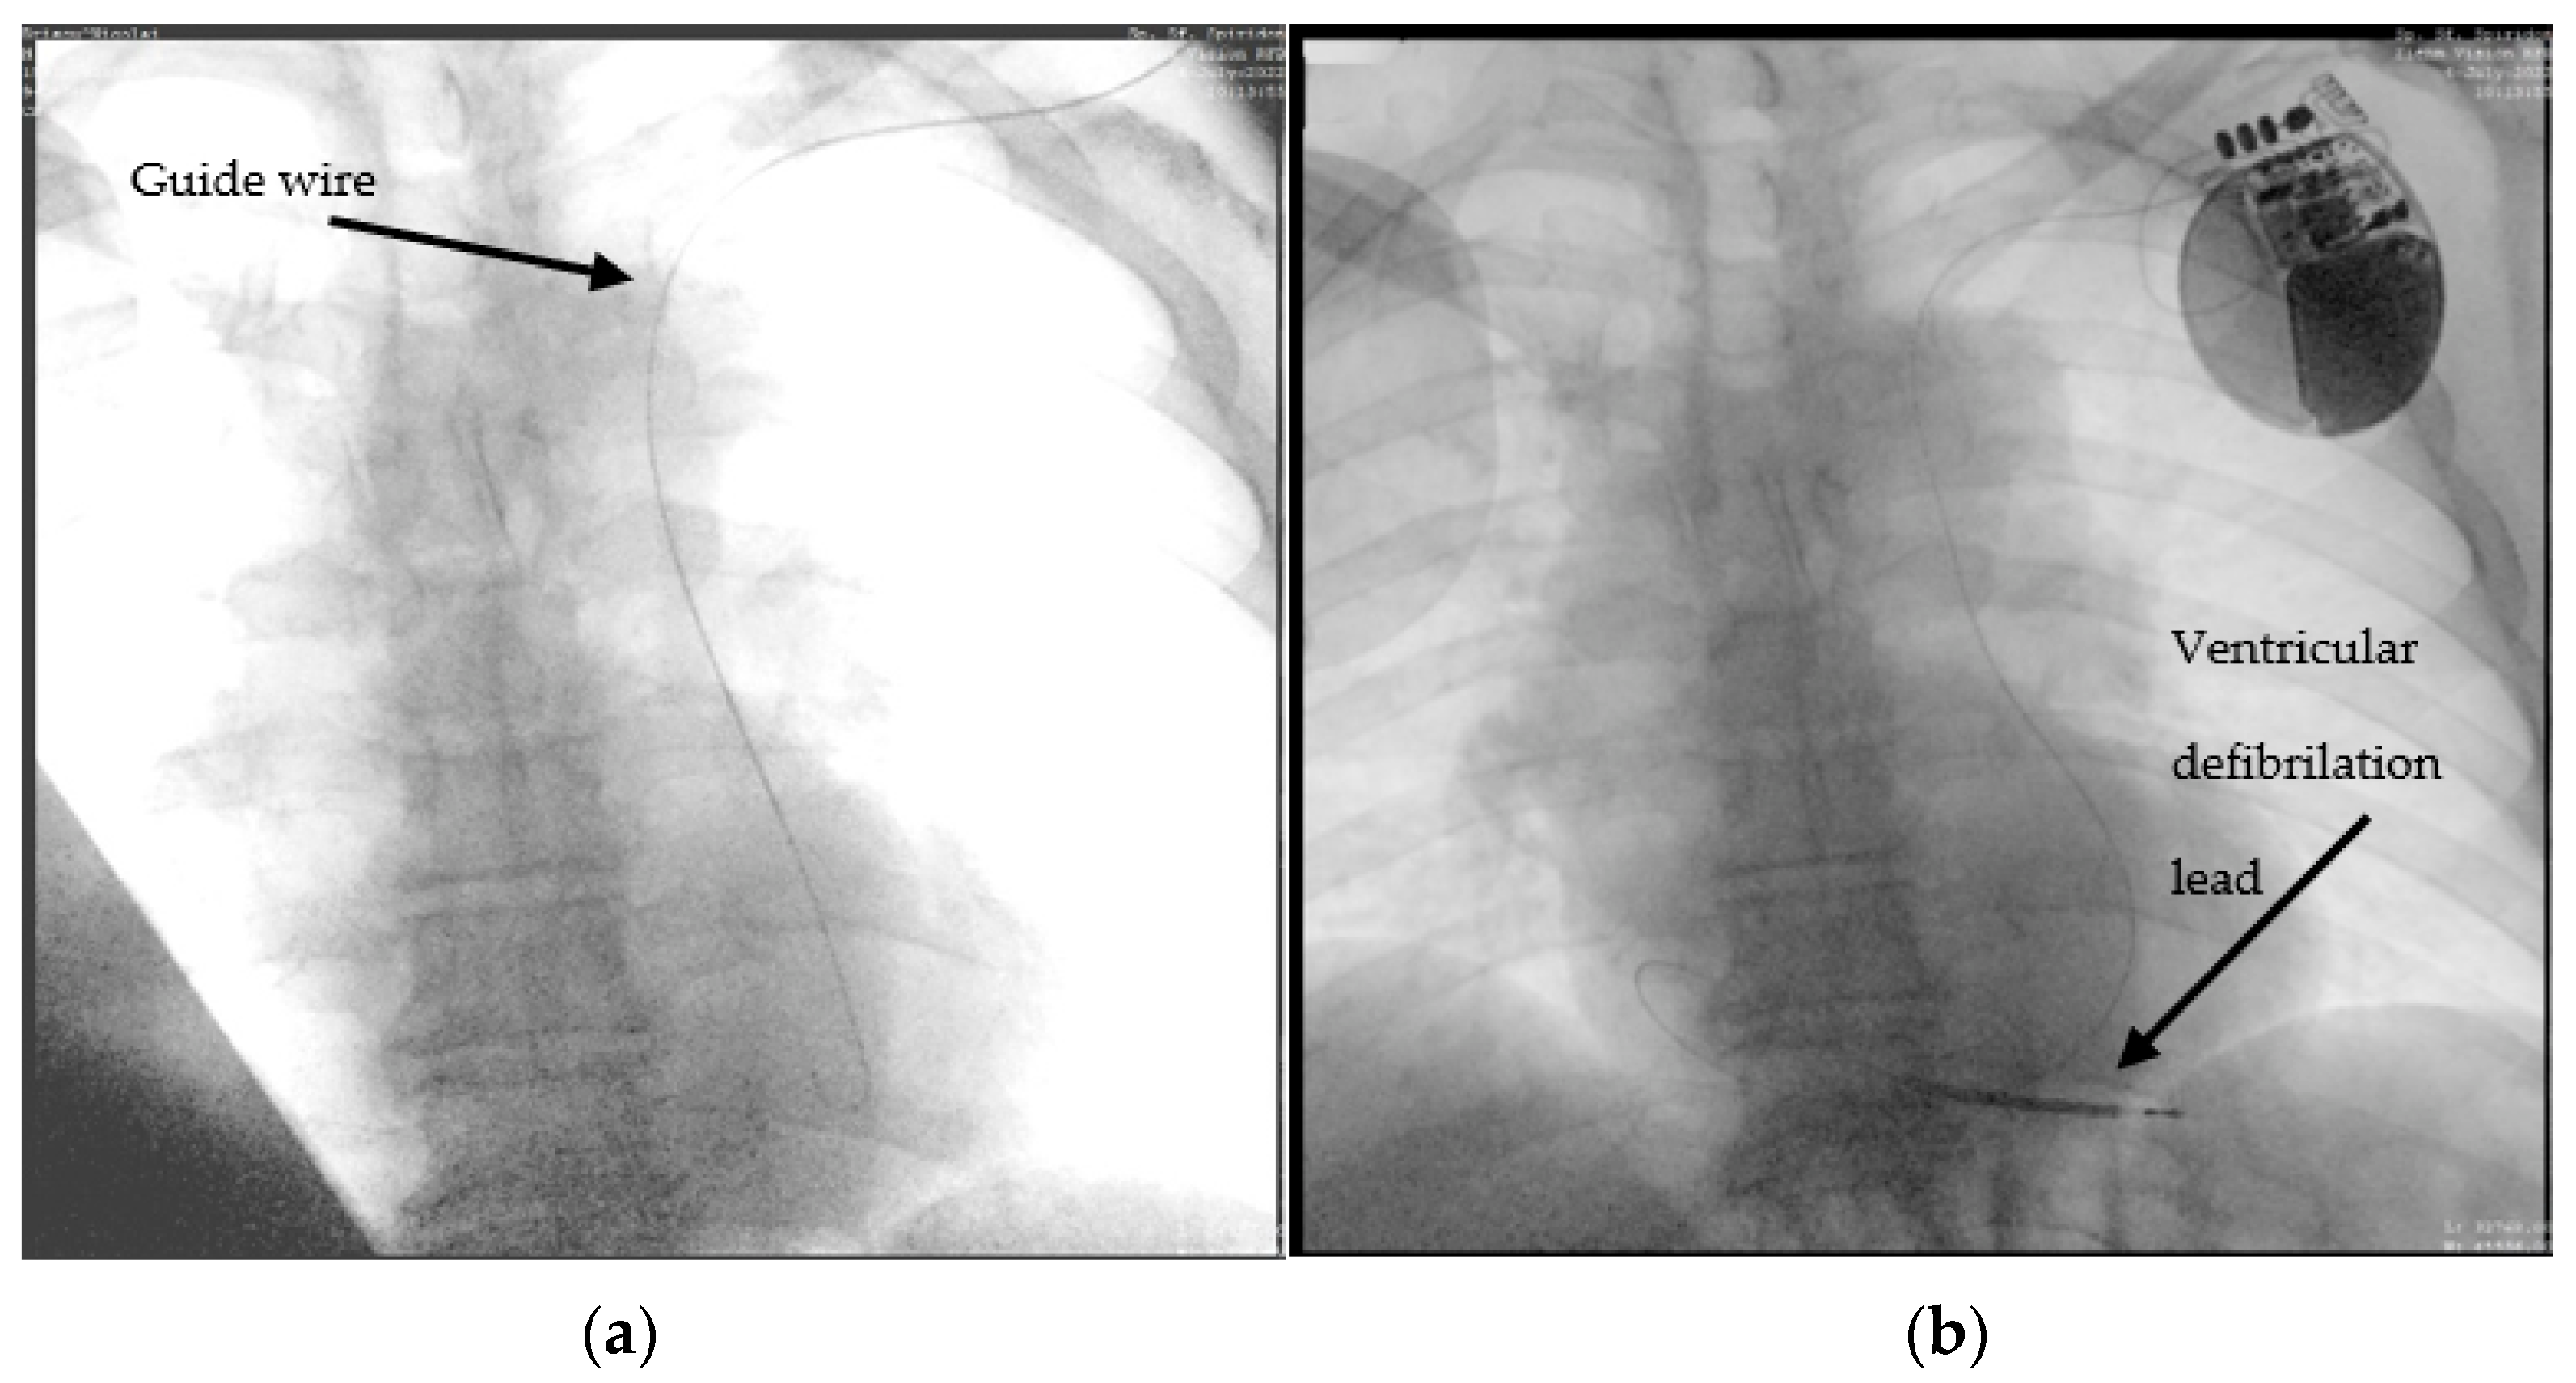

2.1. Case 1. (Type IIIB)